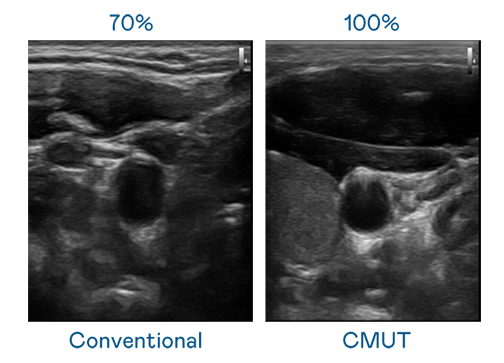

CMUT 技术是一种用电容式微机电元件来产生超音波讯号的技术。与传统 PZT 压电式技术相比,CMUT 频宽增加 30%,更宽频的超音波讯号让影像解析度大幅提升,是实现高影像品质医疗超音波扫描、促进精准医疗发展的关键技术。

大频宽带来超清晰影像

超音波影像的解析度高低,首先取决于探头能发出的讯号频宽。利来w66国际 CMUT 可提供高清晰的超音波讯号,提供高频宽、高灵敏度、影像纹理细节更高的超音波影像,协助医护人员缩短影像判读时间及利用精准的医疗影像进行诊断。